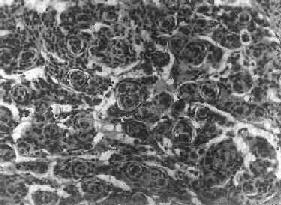

图16-25 室管膜瘤 瘤细胞为圆形或卵圆形,核染色质丰富,胞浆少,可见有细长的胞浆突起与血管相连,呈放射关,形成假菊形团 (二)髓母细胞瘤 髓母细胞瘤(medulloblastoma)好发于儿童,仅次于星形胶质细胞瘤而占第2位,其发生率占儿童颅内肿瘤的25%,发病年龄75%为15岁以下,偶见于成人,男性较女性为多(2~3:1)。 本瘤来源于小脑蚓部的原始神经上皮细胞或小脑皮质的胚胎性外颗粒层细胞,故本瘤主要见于小脑,在儿童多发生于小脑蚓部,在成人则多见于小脑半球。 肉眼观,瘤组织呈鱼肉状,色灰红。镜下,肿瘤由圆形、椭圆形或胡萝卜形细胞构成,胞核着色深,胞浆少而边界不清楚,有多少不等的核分裂像。细胞密集,间质中有纤细的纤维,血管不多。瘤细胞环绕一个嗜银性纤细的神经纤维中心作放射状排列形成典型的菊形团(图16-26),这对髓母细胞瘤的病理诊断有一定的意义。瘤细胞具有向神经元及神经胶质双向分化的潜能,既能向神经母细胞、节神经细胞分化,也能向胶质母细胞、星形胶质细胞分化。如瘤细胞侵入软脑膜,可在蛛网膜下腔脑脊液中广泛播散转移。

图16-26 髓母细胞瘤 瘤细胞较小,着色深,密集排列,有菊形团形成 髓母细胞瘤恶性程度高,预后差。 (三)脑膜瘤 脑膜瘤(meningioma)可来源于脑膜的各组成成分如蛛网膜细胞,纤维母细胞或血管,其中多数来源于蛛网膜颗粒中的蛛网膜细胞。本瘤大多生长缓慢,良性类型可完全无症状,在70岁以上老人的尸检中,发现无症状的脑膜瘤不在少数,无症状脑膜瘤占颅内肿瘤的14%。脑膜瘤患者多为40~50岁中年人,女性较男性多。 肿瘤的好发部位与蛛网膜颗粒所在部位相同,常见于上矢状窦旁大脑镰两侧,蝶骨嵴,嗅沟,小脑脑桥角;在脊髓则以胸段为多见,一般颅内脑膜瘤较脊髓脑膜瘤多2倍。 肉眼观,肿瘤呈球形,分叶状或不规则形,质实或硬,边界清楚,周围脑组织受压成凹陷切迹(图16-27)。少数肿瘤呈斑块状覆盖较广泛区域,甚至整个脑半球,称为斑块型脑膜瘤。肿瘤质地硬,切面灰白色,呈颗粒状、条索旋涡状,有的质地似砂砾样,乃由于有多量砂粒体存在。